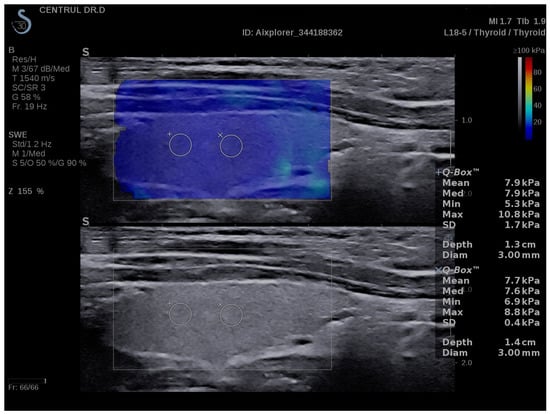

3.2. SWE Measurements

| SWE | Mean EI-THY (kPa) | 13.8 (13.3–17) | 10.1 (9.3–11.2) | <0.0001 |

| Mean EI-LL (kPa) | 13.8 (13.1–17) | 10.4 (9.1–11.2) | <0.0001 | |

| Mean EI-RL (kPa) | 13.9 (13.3–16.6) | 10.2 (9.4–11.1) | <0.0001 | |